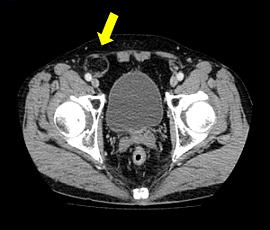

以前より左下腹部に違和感があり受診。精査の結果、左外鼡径ヘルニアと診断。手術(腹腔鏡下ヘルニア手術

(TAPP法))を施行した。

CT画像